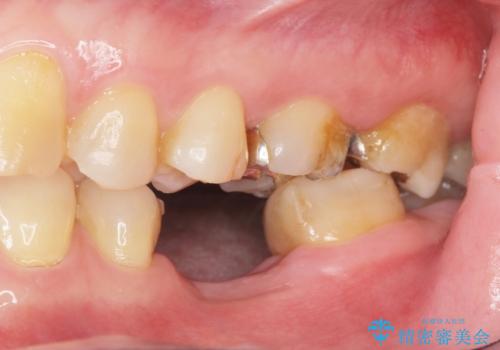

- 歯を破折により失い、インプラント治療を希望され来院されました。

インプラントを適切な位置に埋入することで、清掃性が高くしっかりと咬合力に耐えられるようなインプラント治療を行うことができます。